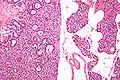

Микропрепарат аденомы паращитовидной железы.